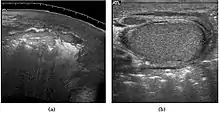

![]() Sonography of a normal testis. The normal testis presents as a structure having homogeneous, medium level, granular echotexture. The mediastinum testis appears as the

hyperechoic region located at the periphery of the testis as seen in this figure. | |

The normal adult testis is an ovoid structure measuring 3 cm in anterior-posterior dimension, 2–4 cm in width, and 3–5 cm in length. The weight of each testis normally ranges from 12.5 to 19 g. Both the sizes and weights of the testes normally decrease with age. At ultrasound, the normal testis has a homogeneous, medium-level, granular echotexture. The testicle is surrounded by a dense white fibrous capsule, the tunica albuginea, which is often not visualized in the absence of intrascrotal fluid. However, the tunica is often seen as an echogenic structure where it invaginates into the testis to form the mediastinum testis. In the testis, the seminiferous tubules converge to form the rete testes, which is located in the mediastinum testis. The rete testis connects to the epididymal head via the efferent ductules. The epididymis is located posterolateral to the testis and measures 6–7 cm in length. At sonography, the epididymis is normally iso- or slightly hyperechoic to the normal testis and its echo texture may be coarser. The head is the largest and most easily identified portion of the epididymis. It is located superolateral to the upper pole of the testicle and is often seen on paramedian views of the testis. The normal epididymal body and tail are smaller and more variable in position.